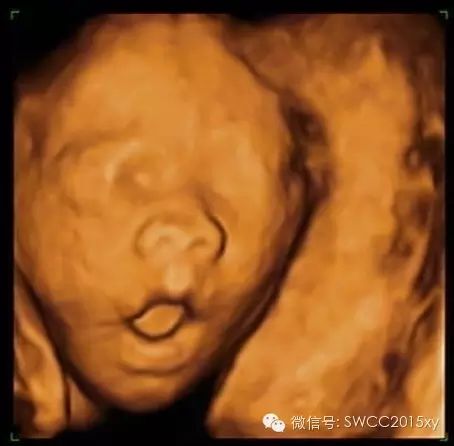

看我皱了一下眉,哦原来我是中国的宝宝,我不是西方的亚当,原来都是妈妈缺钙引起的。因此我们在判断胎儿是否缺钙,不仅仅是看胎儿的长骨的钙化程度和双顶径与股骨的比值,还可以利用现代先进的医学来判断,四维彩超的透明模式来看胎儿的肋骨发育提供更加准确、全面、科学的诊断依据,为减少先天性佝偻病做出应有的贡献。所以准妈妈一定要注意营养、规律、全程、有效补钙哦。